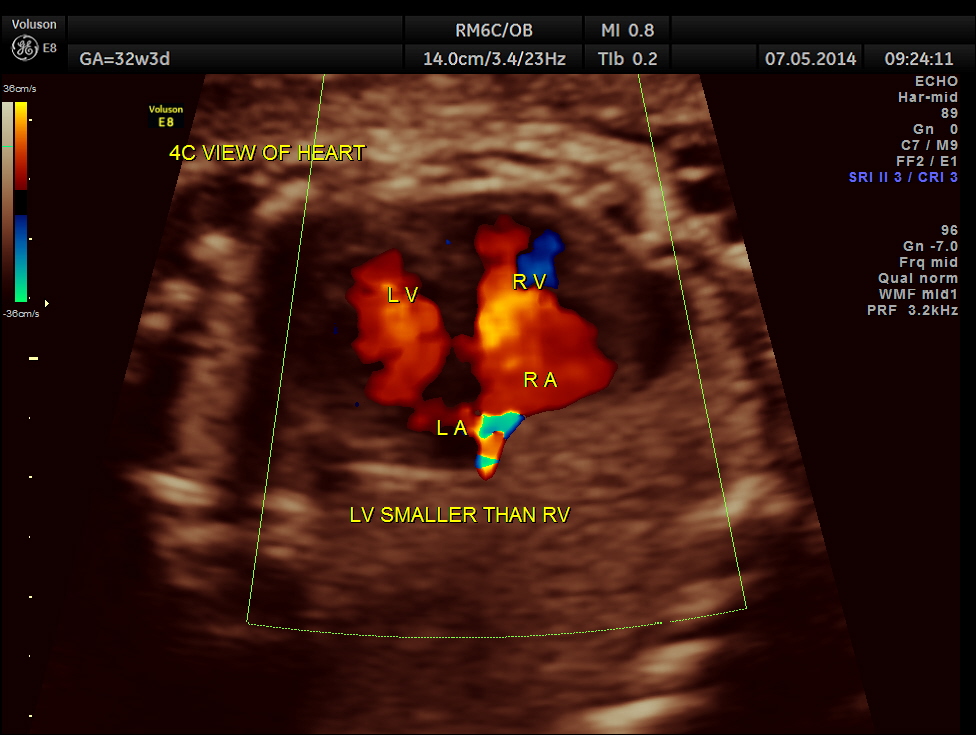

The 4 chamber view shows enlarged RA and RV and a confluence venous chamber behind the left atrium.

LA & LV appear to be smaller than RA & RV.

No definitive pulmonary vein draining into the left atrium could be made out . A common transverse vessel was seen beneath the left atrium . The LA & RA were smaller than the RA. Similarly the Aorta and the aortic arch were smaller than the pulmonary artery and the ductal arch due to the increased flow in the right side.